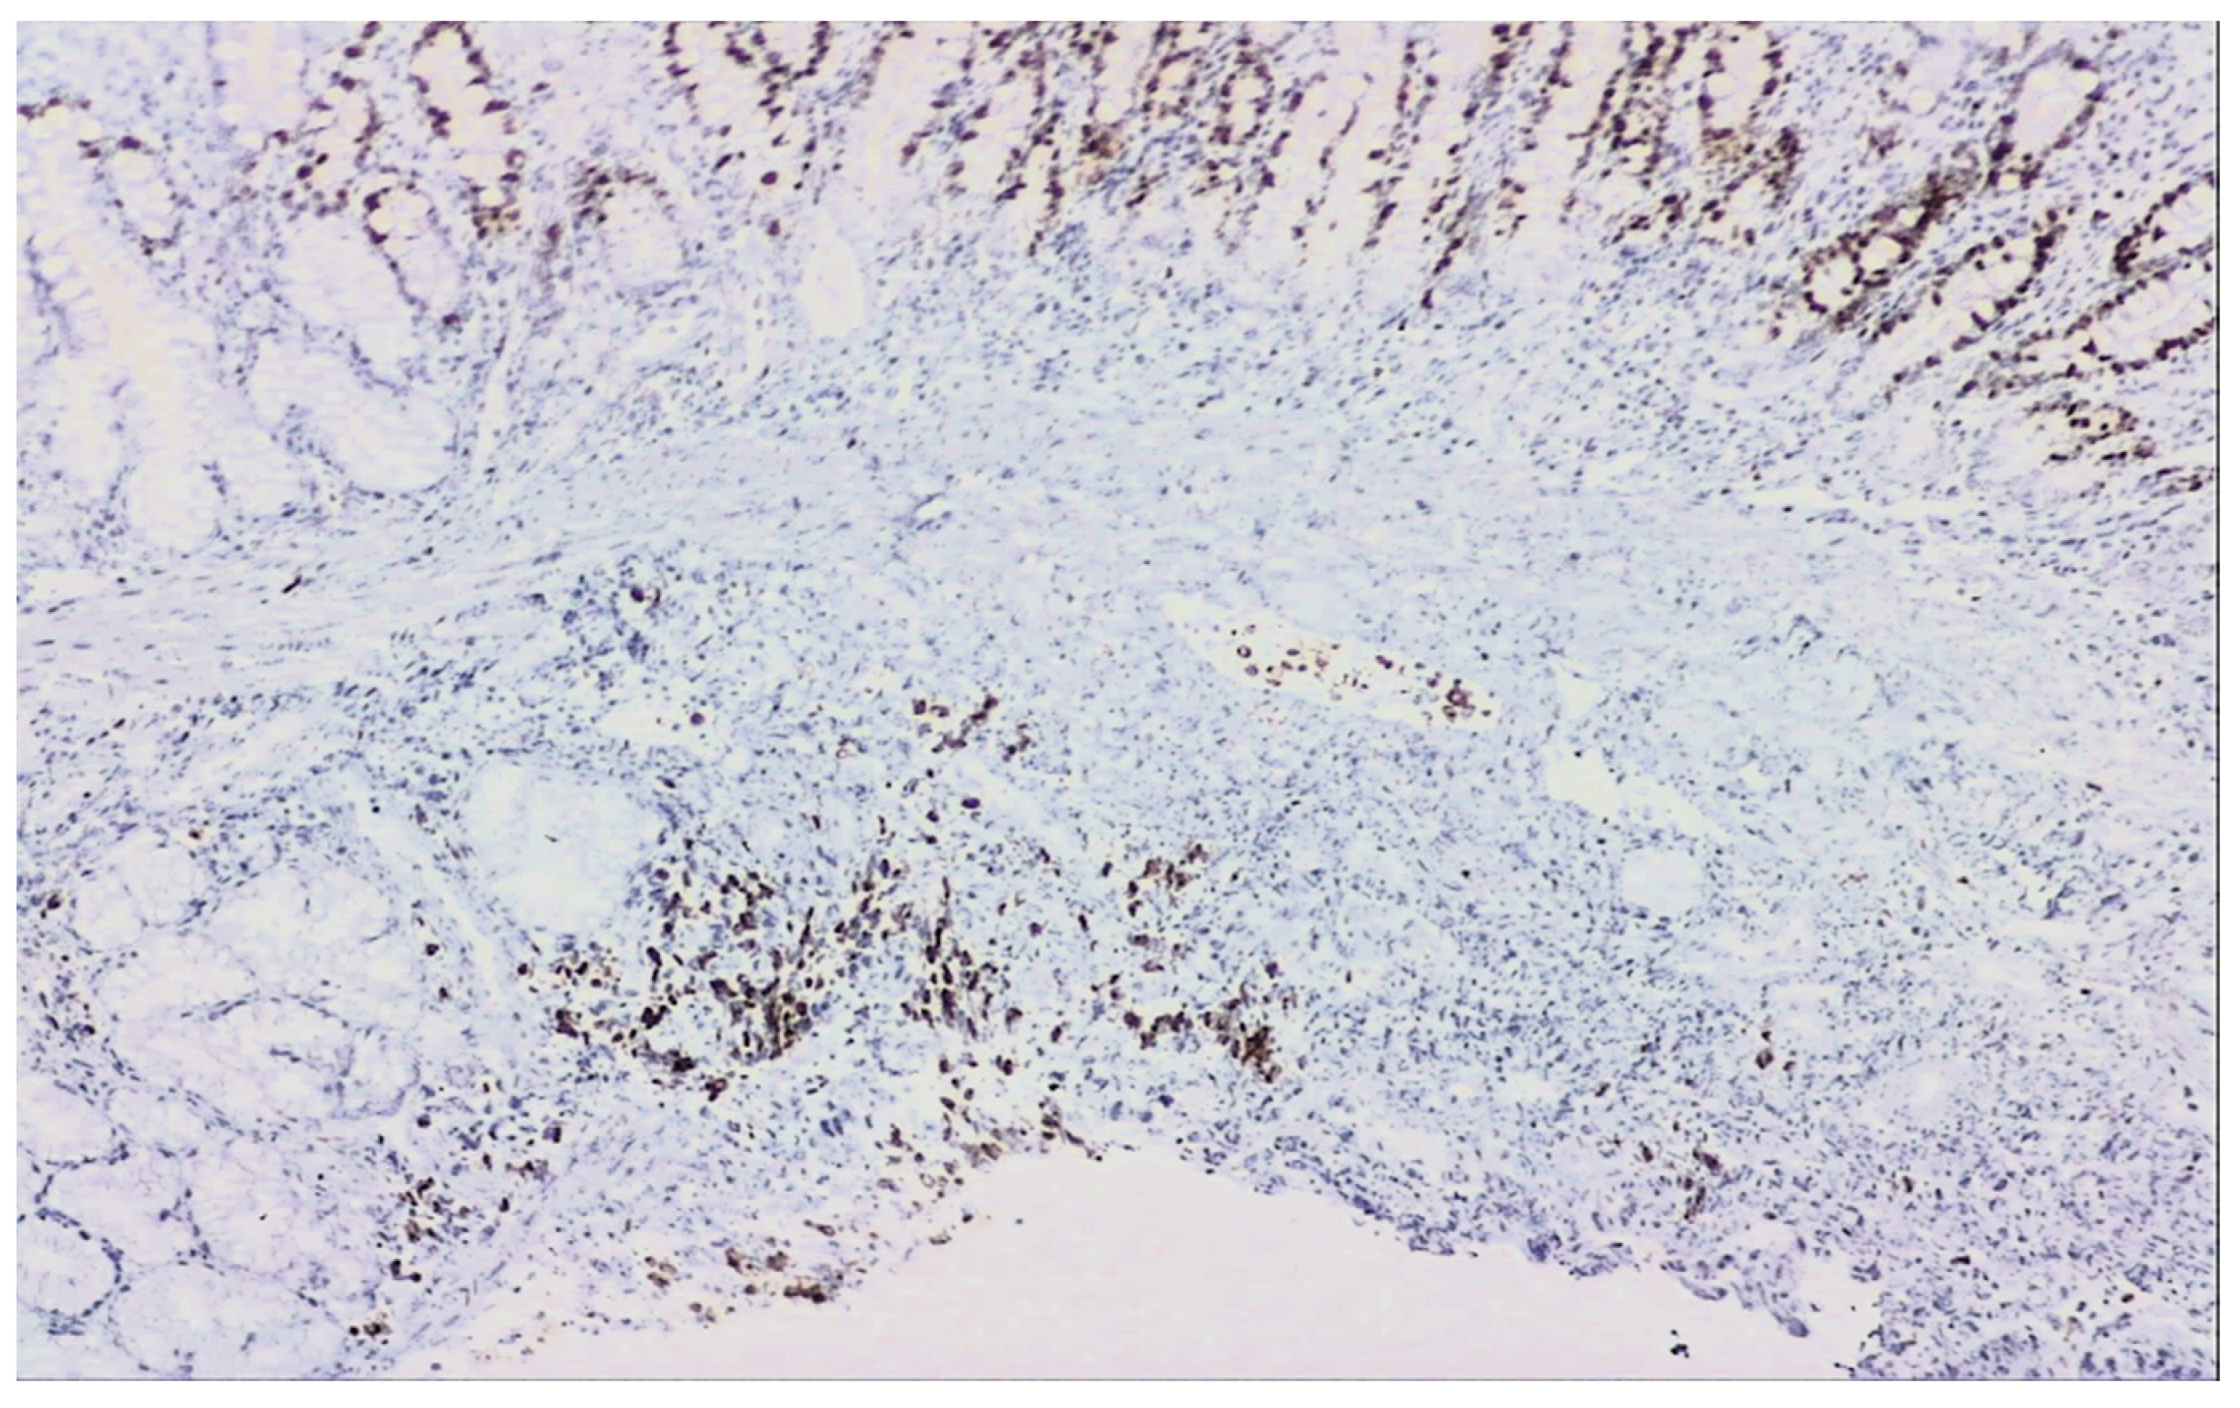

2. Detailed Case Description

2.1. Diagnostic Evaluation